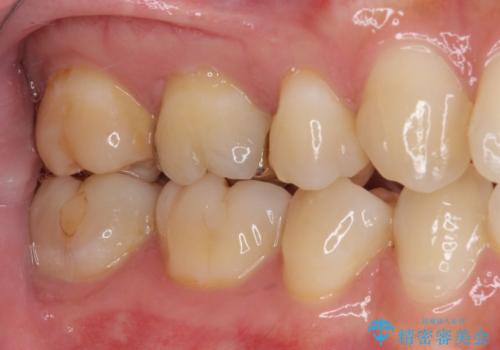

セラミッククラウンを装着する前に仮歯を装着しましたが、その時点で強い痛みはほぼ改善され、セラミッククラウン装着後には痛みはもちろん、しみる症状も感じることがなくなりました。